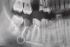

A cracked tooth is one of the most common forms of tooth pain toothache. As shown in the broken tooth model to the left, it is often caused by silver amalgam fillings in the teeth and the sharp edge that used to lock the filling into place. This edge is weakened, and it results in a cracked tooth. If the tooth cracks above the gun, it can be repaired with a ceramic dental crown. Otherwise, it might need a root canal treatment. When a dental crown is cemented onto the broken tooth to hold the pieces together, it behaves like a crash helmet and gives it strength.

The process requires drilling down the tooth and removing the nerve and filling the tooth right down to the root to prevent any new infection or decay from below.